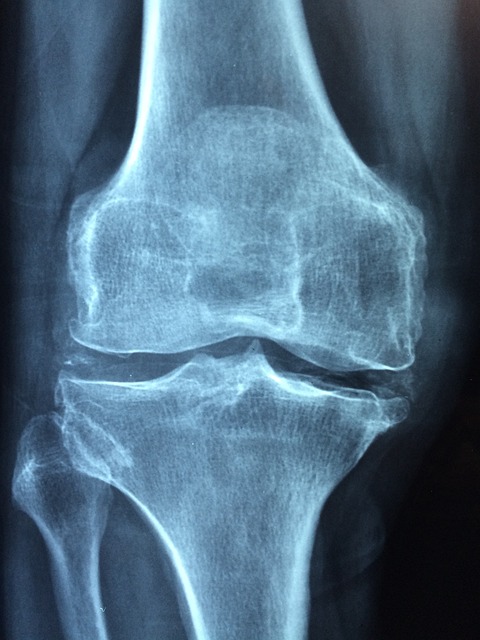

골다공증은 ‘조용한 질환’이라고 불릴 만큼 뚜렷한 증상이 없이 진행됩니다. 그렇기 때문에 뼈밀도 측정을 통해 현재 상태를 정확히 파악하고, 그에 맞는 생활습관을 실천하는 것이 중요합니다. 뼈밀도(BMD, Bone Mineral Density) 검사는 뼈 속 무기질의 양을 측정하여 골다공증 유무와 위험도를 평가하는 방법입니다. 가장 일반적으로 사용되는 방법은 이중에너지 X선 흡수계측법(DEXA)으로, 주로 척추, 고관절 등의 뼈 밀도를 측정합니다. 정상 범위는 T-값 기준으로 -1.0 이상이며, -1.0 ~ -2.5 사이는 골감소증, -2.5 이하일 경우 골다공증으로 진단됩니다. 특히 폐경 이후 여성, 65세 이상 고령자, 과거 골절 이력이 있는 사람은 정기적인 뼈밀도 검사를 권장합니다. 뼈밀도를 유지하기 위해서는 위에서 언급한 영양과 운동 외에도 생활습관 개선이 필요합니다. 흡연과 과도한 음주는 뼈 건강에 악영향을 주며, 카페인 역시 칼슘 배출을 촉진하므로 과다 섭취를 피해야 합니다. 또한, 체중 유지도 중요합니다. 과체중은 관절에 부담을 주지만, 저체중은 오히려 뼈에 가해지는 자극이 적어 골밀도 감소 위험이 커질 수 있습니다. 따라서 적정 체중을 유지하는 것이 가장 바람직합니다. 무엇보다 중요한 점은, 뼈 건강은 하루 아침에 만들어지는 것이 아니라는 점입니다. 뼈는 30대 중반 이후 서서히 밀도가 줄어들기 시작하므로, 젊은 시절부터 철저한 관리가 필요합니다. 특히 폐경기 전후 여성은 뼈 손실 속도가 빨라지므로 더욱 철저한 예방이 필수입니다.